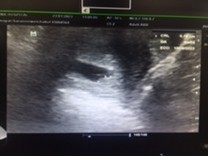

ของเราซาวด์ตอน6W เจอแต่ถุงตั้งครรภ์ค่ะ

ตอน 6 วีค บ้านนี้เห็นแค่หัวใจน้องค่ะ

ไม่เห็นค่ะ เห็นแค่ถุงอย่างมาก

บ้านนี้6w6dค่ะ